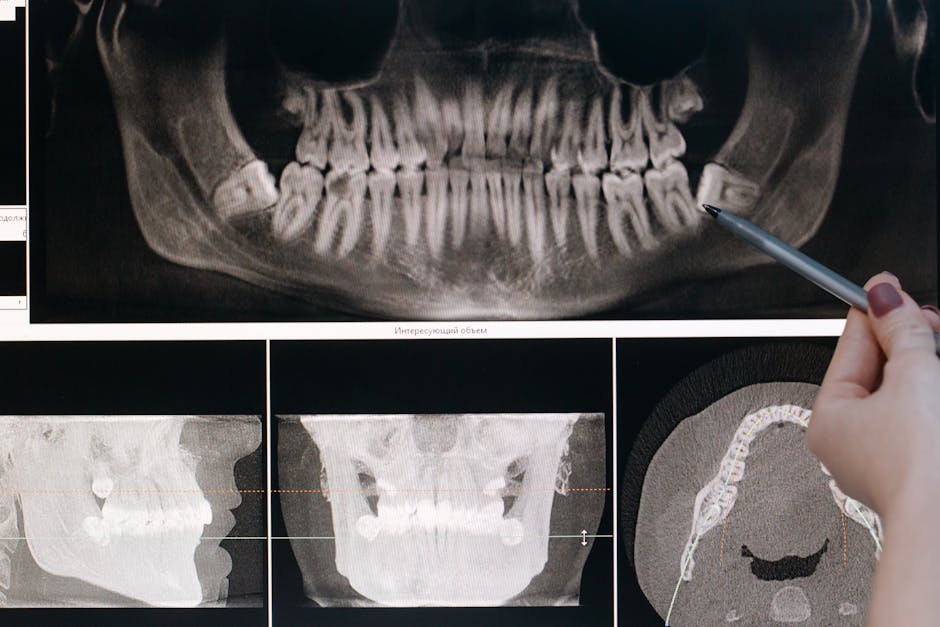

In dental terms, misaligned teeth create real problems beyond aesthetics. They can make proper cleaning difficult, leading to decay and gum disease. They might cause abnormal wear on tooth surfaces or even contribute to jaw pain and TMJ disorders. That's why at Logan Dental Care, we take alignment seriously—it's about health, not just appearance.

First, we'll meet for a friendly consultation to see if clear aligners are right for you. If they are, we'll take precise 3D scans of your teeth—no more goopy impressions that make you gag! These digital models help us map out exactly how your teeth will move over time.

Then comes the exciting part—receiving your custom-made clear trays. Each aligner is designed to shift your teeth approximately 0.25 mm before you move to the next one. It's like a choreographed dance where each tiny movement brings your smile closer to perfection.

Most patients wear each set for about two weeks, keeping them in for 20-22 hours daily. The entire treatment typically takes 12-18 months, though some people see results sooner. Throughout your journey, we'll check in regularly to ensure everything's progressing beautifully.